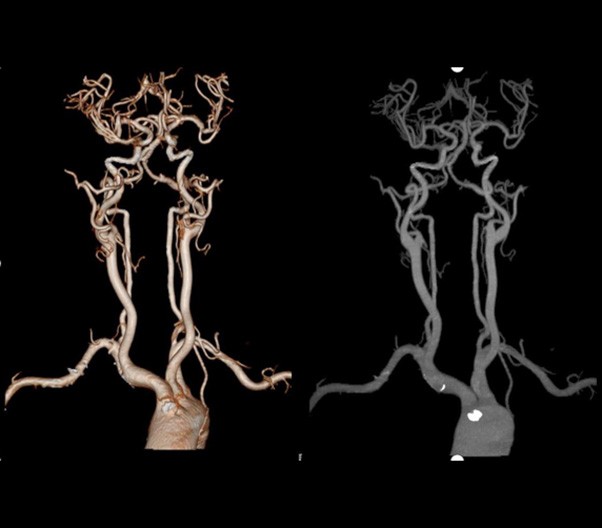

臨床畫廊